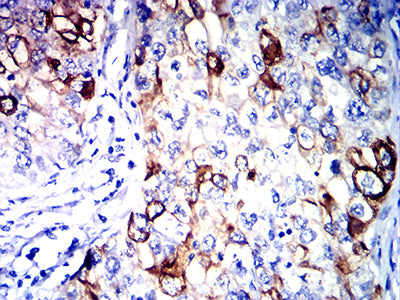

分类: 科研抗体货号: 32039别名: ILT3; LIR5; LILRB4; ILT-3; LIR-5应用: IHC,IF,FCM反应种属: Human